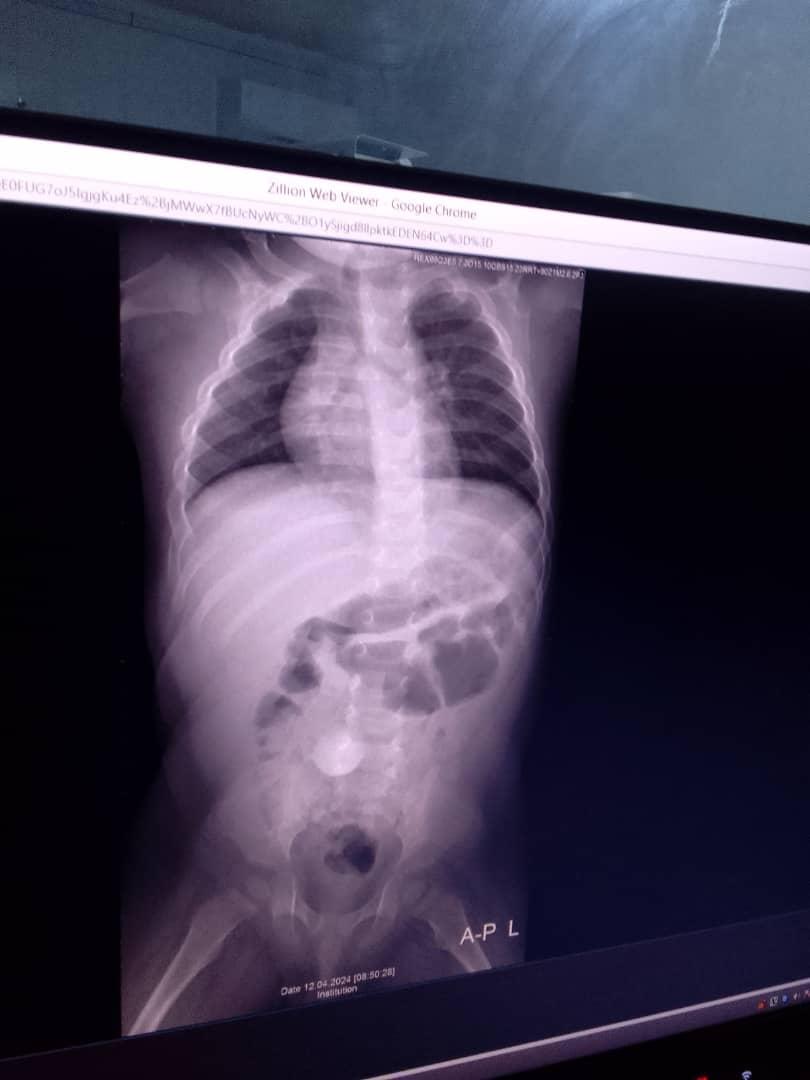

In an exclusive interview with this medium, Isha Turay, mother of the six month old Mamoud Kondeh says her baby was hit with a Stone on the neck by one Isatu S. Kamara, the wife of Abdul Camilo Kamara, a senior member of the Sierra Leone People’s Party in the Northern District of Bombali, Jeneba S. Ellie and Kadiatu Bangura, all members of the same family.

It was during this altercation, Turay said the wife of the said SLPP stakeholder in Makeni pelted a stone that strike her six months old baby leaving him with a fractured neck. Though she reported the matter to the Mena Police Station in Makeni, the family, she said is bragging that nothing will come out of the matter.

They boy, he said has been with a neck problem since his birth.